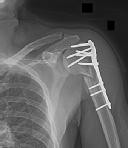

Figure 1 is the radiograph of a 49-year-old man who sustained a closed injury to his

left shoulder in a motor vehicle collision. He underwent uncomplicated ORIF (see Figure 2), but at his first post-operative visit he had persistent pain and deformity (see Figure 3). What is the primary factor contributing to this complication?